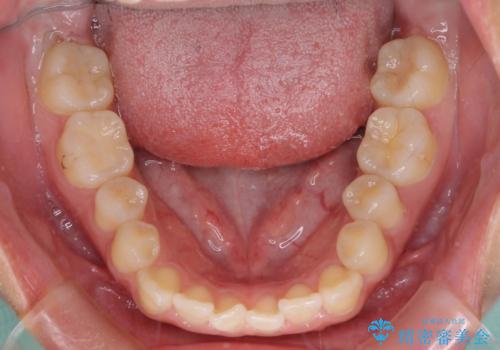

- 上下の前歯が非接触であることと、それに伴う口元の閉じにくさを気にして来院された患者様です。

奥歯の咬み合わせを見ると、上顎が下顎に対して相対的に前方にありました。

口元の閉じにくさを改善するためには、上顎臼歯を後方に移動させた咬み合わせにする必要があります。

インビザライン単体で改善することも可能ですが、達成する可能性が高くないため、カリエールディスタライザーという補助装置を併用して、より確実性を上げることとしました。

奥歯の咬み合わせを改善しながら、並行してインビザラインで歯列を整えることとしました。